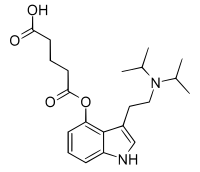

4-Hydroxy-N,N-diisopropyltryptamine (4-HO-DiPT or Iprocin) is a synthetic psychedelic drug. It is a higher homologue of psilocin, 4-HO-DET, and is a positional isomer of 4-HO-DPT and has a tryptamine molecular sub-structure.

Clinical trials

FT-104, a prodrug to 4-HO-DiPT, has entered double blind, randomized, placebo controlled, phase 1 clinical trials in healthy volunteers at the Royal Adelaide Hospital in Australia for the treatment of postpartum depression and treatment-resistant depression. [6][7][8] It is propably a less neurotoxic alternative to alpha-Methyltryptamine (αMT, AMT, Indopan) and alpha-Ethyltryptamine (αET, AET, Monase).